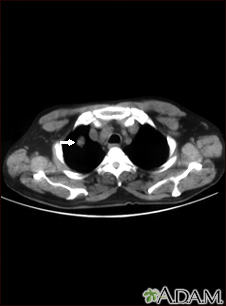

Pulmonary nodule, solitary - CT scanBackPulmonary nodule, solitary - CT scanThis CT scan shows a single lesion (pulmonary nodule) in the right lung. This nodule is seen as the light circle in the upper portion of the dark area on the left side of the picture. A normal lung would look completely black in a CT scan. E-mail FormEmail ResultsName:Email address:Recipients Name:Recipients address:Message: